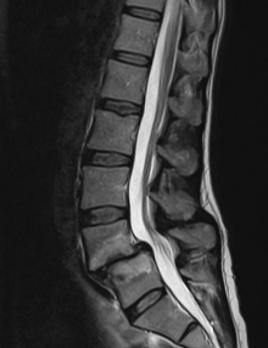

Het ‘zware’ leven van de lumbale disci intervertebrales (BD) Lees meer over Het ‘zware’ leven van de lumbale disci intervertebrales (BD) Het ‘zware’ leven van de lumbale disci intervertebrales (BD)

Dit artikel is het laatste deel van het drieluik over het ‘zware’ leven van de lumbale disci intervertebrales. In deel 1­ (editie ­2020-3­ van­ Physios) ­zijn­ de­ bouw, ­functie ­en ­de­ bloed-­ en ­zenuwvoorziening ­van ­de ­lumbale­ discus beschreven­ en ­is ­het ­verschil ­tussen discusdegeneratie­ en­ discusveroudering­ belicht.­ Deel­ 2­ (editie­ 2021-4­ vanPhysios) is ingegaan op verschillende aspecten van discusdegeneratie. Er zijn morfologische kenmerken van discusdegeneratie besproken, het veranderde mechanische gedrag van een discus met discusdegeneratie is beschreven, en besproken is hoe zowel mechanische als biologische factoren een rol spelen in de progressie van discusdegeneratie. Deel ­3­ staat ­eveneens ­in­ het­ teken­ van­ discusdegeneratie.­ Het ­artikel­ start­ met­ de ­oorzaken­ van het­ ontstaan ­van discusdegeneratie. Hierbij spelen niet mechanische factoren de belangrijkste rol, zoals vaak gedacht wordt, maar juist genetische factoren. Al jaren is bekend dat het op individueel niveau niet mogelijk is om aan de hand van de ernst van discusdegeneratie, vastgesteld via beeldvorming, te voorspellen of de persoon asymptomatisch (zonder lage rugpijn) of symptomatisch (met lage rugpijn) is. Maar wat maakt dan wel het verschil? Na een poging tot een antwoord op deze vraag sluit het artikel af met de beschrijving van de fysiotherapeutische behandeling van een patiënt met lage rugpijn op basis van discusdegeneratie.